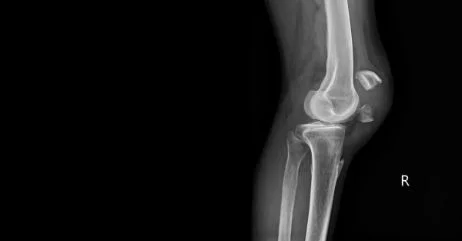

Frattura da stress al ginocchio

Provoca dolore nella parte anteriore o laterale del ginocchio, che peggiora durante i piegamenti o la corsa in discesa. È più frequente nei saltatori o nei giocatori di basket e volley.

La diagnosi della frattura da stress si basa su anamnesi accurata, esame clinico e test di imaging come:

- risonanza magnetica: l’esame di riferimento, in grado di rilevare anche le microlesioni ossee precoci;

- radiografia: nelle fasi iniziali può anche essere negativa, poiché la frattura non è ancora visibile;

- scintigrafia ossea o TAC: utili nei casi dubbi o per valutare l’estensione del danno.